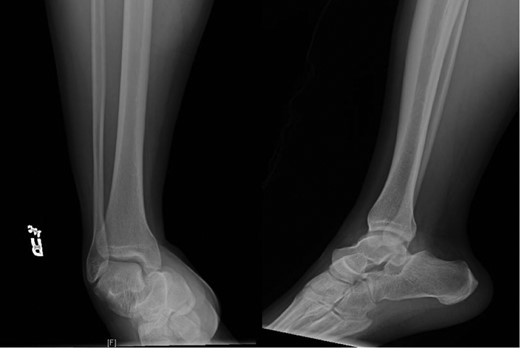

Once general anesthesia was induced, closed reduction was attempted using axial traction with the knee in flexion. Closed reduction was unsuccessful once again (Fig. 3) so the decision was made to attempt open reduction. An anteromedial approach was used dissect down to the talonavicular joint. Retractors were placed with care to avoid injury to tibialis anterior tendon or superficial peroneal nerve. The joint capsule was seen to be disrupted and further exposure revealed a thin, coronal fracture of the anteromedial aspect of the talar head measuring roughly 2 cm in length and 6 mm in thickness (Fig. 4). Once this fragment was removed, the subtalar and talonavicular joints were easily reduced. It was thought that this incarcerated fragment was the likely cause for the unsuccessful closed reduction. The talar head fragment was unamendable for stabilization due to its small size with poor healing potential, thus it was removed. The talonavicular joint was then percutaneously pinned in retrograde fashion with three K-wires (Fig. 5) to maintain anatomic reduction of the subtalar and talonavicular joints and the foot was splinted. At 2 weeks follow-up the patient was doing well and radiographs revealed no interval loss of reduction (Fig. 6).

Intraoperative AP view localizing the medial subtalar dislocation.